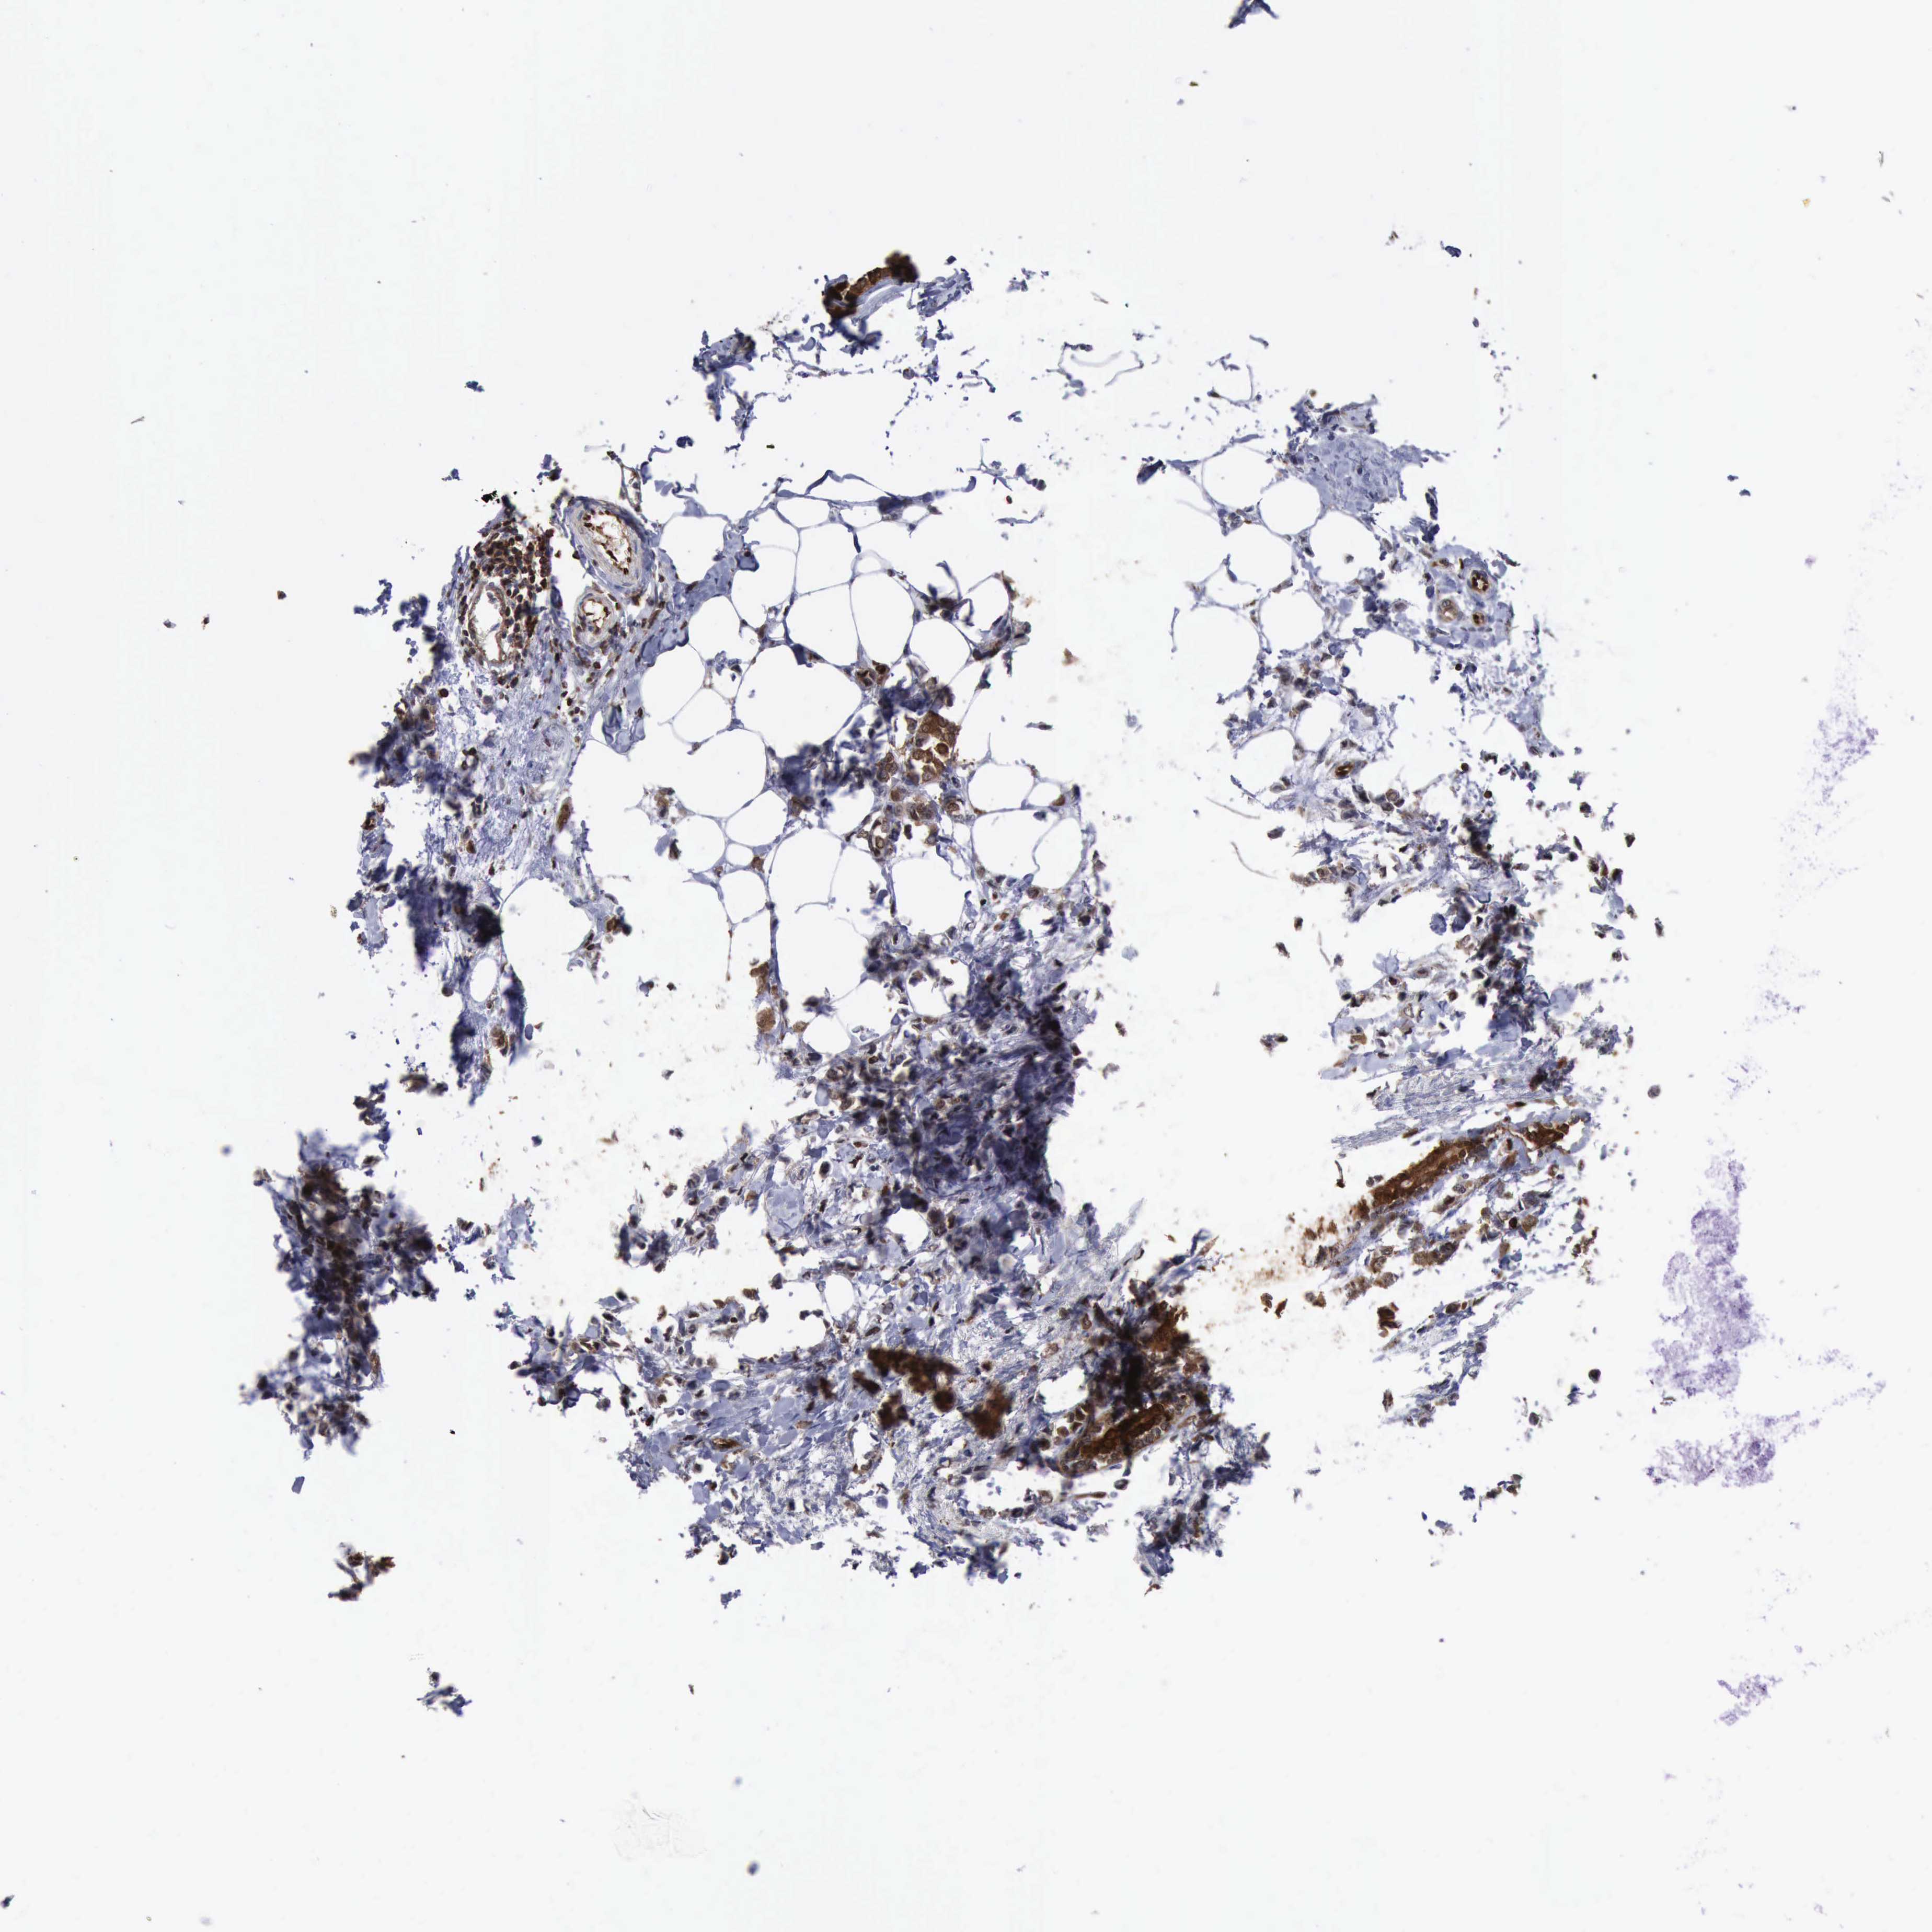

CANCER BREAST CANCER Show tissue menu

BRCA TCGA BRCA VALIDATION PROTEIN EXPRESSION